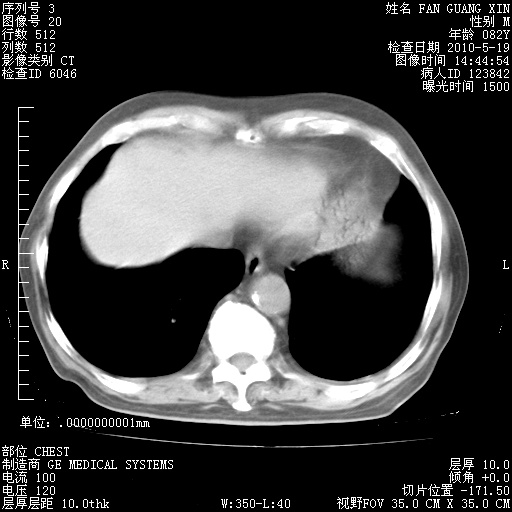

发表于 2010-5-19 19:23

还需要哪些辅助检查?我们医院排除真菌感染没有任何检验方法,胸片好像能够排除肺部真菌感染。